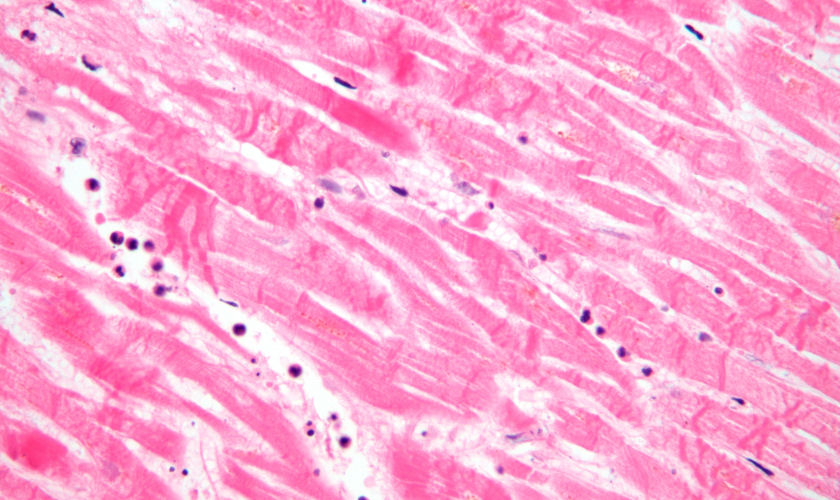

Acute myocardial infarction

Source: MI with contraction bands very high mag.jpg Date: 6 August 2009 Author: Nephron Licence: Creative Commons Attribution-Share Alike 3.0 Unported